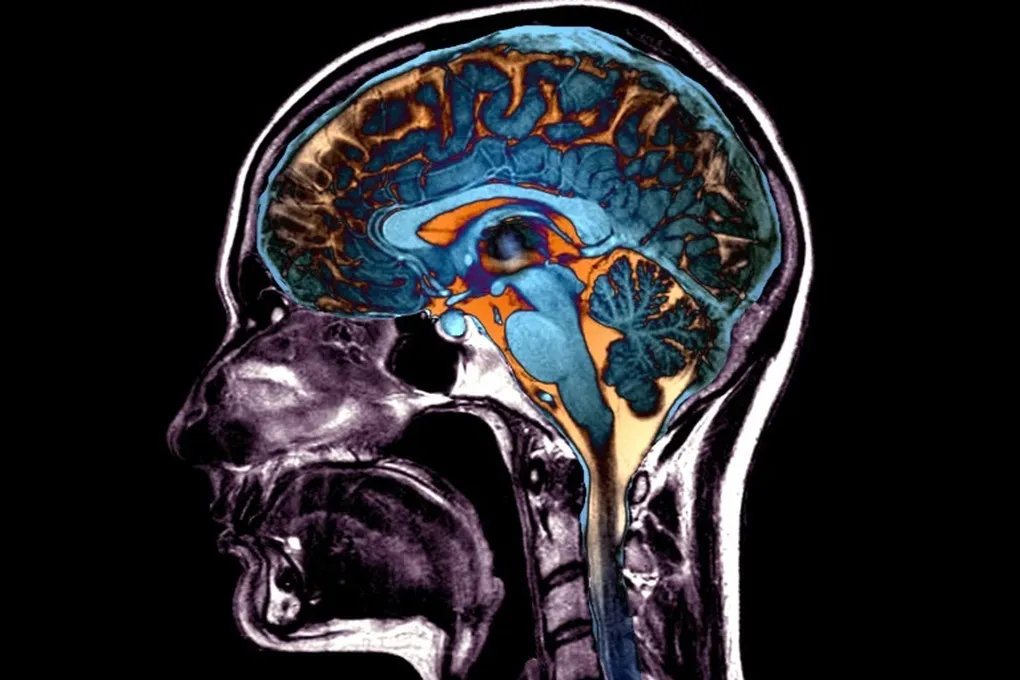

Анализ МРТ-снимков огромной армии добровольцев выявил пять чётких паттернов, по которым мозг уменьшается с годами или под натиском нейродегенеративных болезней. Эти паттерны не просто абстракция — они напрямую связаны с факторами риска, которые частично в нашей власти. Работа, занявшая у команды около восьми лет, опубликована в авторитетном Nature Medicine.

Старение меняет не только кожу. Мозг тоже теряет объём, некоторые его области как бы усыхают. Но эти изменения коварны — они микроскопические. «Человеческий глаз просто не способен уловить такие системные закономерности», — признаётся соавтор исследования Христос Давацикос. Нужен был новый, более зоркий «взгляд».

Команда использовала специально разработанный сложный алгоритм, который сначала обучили на снимках мозга как здоровых молодых людей, так и пожилых, включая тех, у кого уже начались когнитивные проблемы. По сути, алгоритм научили видеть, какие области мозга стареют «хором», а какие — по отдельности. Это позволило создать внутреннюю карту типичных возрастных изменений.

Затем эту карту наложили на снимки почти 50 тысяч человек из различных биобанков и исследований. Так и проступили пять различных сценариев, по которым мозг может терять свою субстанцию.